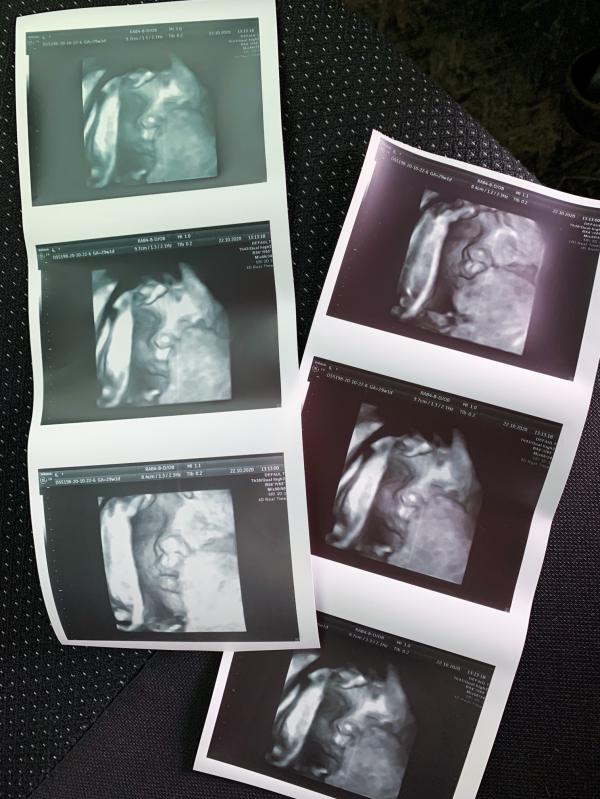

Мы уже совсем скоро родимся

МесЯцев 6 у нас проблема с выбором имени

Как же приятно выходить после УЗИ счастливой с улыбкой до ушей, как вспомню свой второй скрининг вообще ужас( хотя не менее лучший врач был), вышла будто ведро помоев вывалили на тебя.. и ты ещё за это заплатил🙄.

По этому, если идти, то только туда, где ты уже был и знаешь, как все будет проходить.

Все прошло, как и в первую беременность прекрасно, хоть и доча уже закрылась , все равно нам показали ее и сделали хорошие снимки... 😊

Мы как увидели с мужем на экране дочку, сразу сказали друг д...